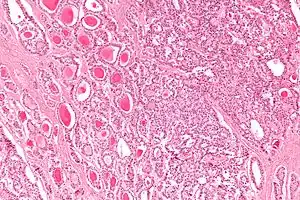

The strumal carcinoid is a type of monodermal teratoma with histomorphologic features of (1) the thyroid gland and (2) a neuroendocrine tumour (carcinoid).[1][2]